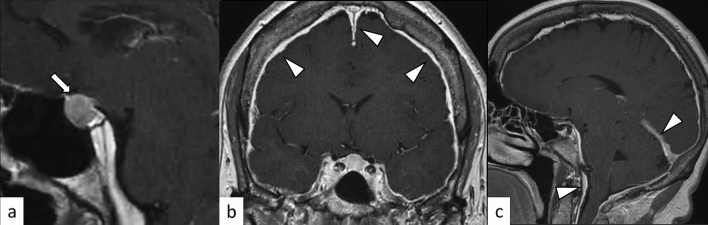

Fig. 19.

A 33-year-old woman with Sheehan’s syndrome after a cesarean section with massive blood loss. The size of the pituitary gland is within normal limits. The anterior pituitary lobe shows hyperintensity on T2-weighted coronal image (a, arrow), isointensity on T1-weighted coronal image (b, arrow) without contrast enhancement (c, arrow)

Fig. 20.

A 62-year-old woman with spontaneous intracranial hypotension. An enlarged pituitary gland is observed on post-contrast T1-weighted sagittal image (a, arrow). Diffuse dural thickening and linear enhancement in both supra- and infratentorial regions are observed (b, c, white arrowheads). A slight downward displacement of the structures appears near the base of the brain, including the hypothalamus, midbrain, pons, and cerebellum